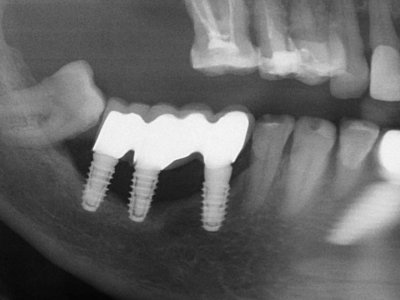

Наличие и степень поражения кости определяется при помощи рентгенологического исследования либо 3D-томографии.